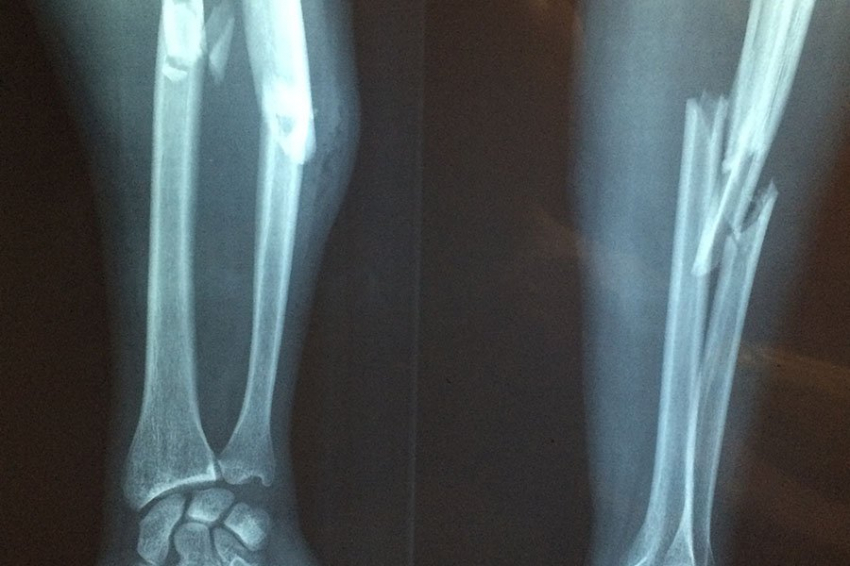

Микробиота кишечника связана с риском переломов

Фото из открытых источников В недавнем исследовании, опубликованном в журнале npj Biofilms Microbiomes, ученые изучили связь между составом кишечной микробиоты (КМ) и частотой переломов в когорте участников Финской программы мониторинга рисков (FINRISK). Переломы вследствие хрупкости костей, часто вызываемые...